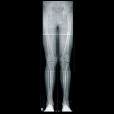

Immagini di alta qualità. Bassi dosaggi. Flusso di lavoro efficiente. DX-G: un livello a parte.